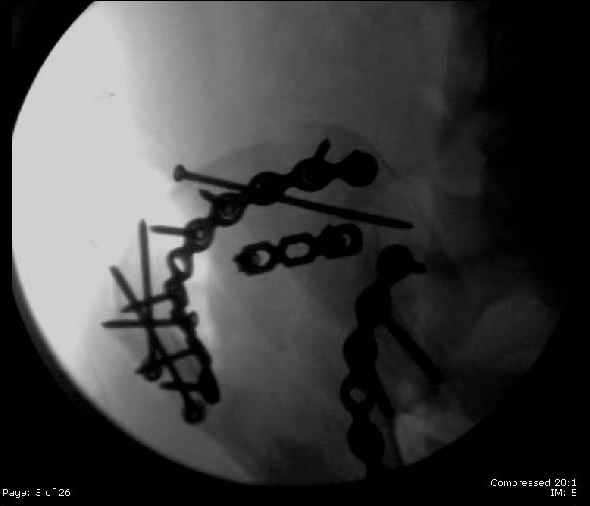

Here are the postop fluoros.

First exposed symphysis & clamped w/Faraboeuf as close to anatomic as possible.

Then extended to R ilioinguinal,really just the lateral window.

Reduced the triangular wedge piece of iliac wing to posterior intact ilium (crescent), held w/k-wire, then used 3-hole push plate to keep from moving, lagged from lat-med w 3.5 screw.

Then 6-hole plate along brim with 1 screw in R sacral ala. Then lagged 2 screws along crest A --> P. finally 10-hole plate along inner aspect of crest. R posterior ilium still a bit stepped off.

Symphysis then 'fine-tuned' & reduced as close as possible to anatomic (but, still with forward rotation of R hemipelvis - or, is it extension?) Accepted that amount of deformity and plated symph

with 4-hole symphyseal plate.

Fluoroed L SI joint and it seemed stable, but wide. So, applied c-clamp to try to squeeze down L SI joint (and note, on the last slide attached, that it's still wide), and got it closer. Single perc Iliosacral screw 40mm thread.

Applied second plate anteriorly on symphysis as I wasn't confident L SI was as stable as it could be and wanted to protect it better.